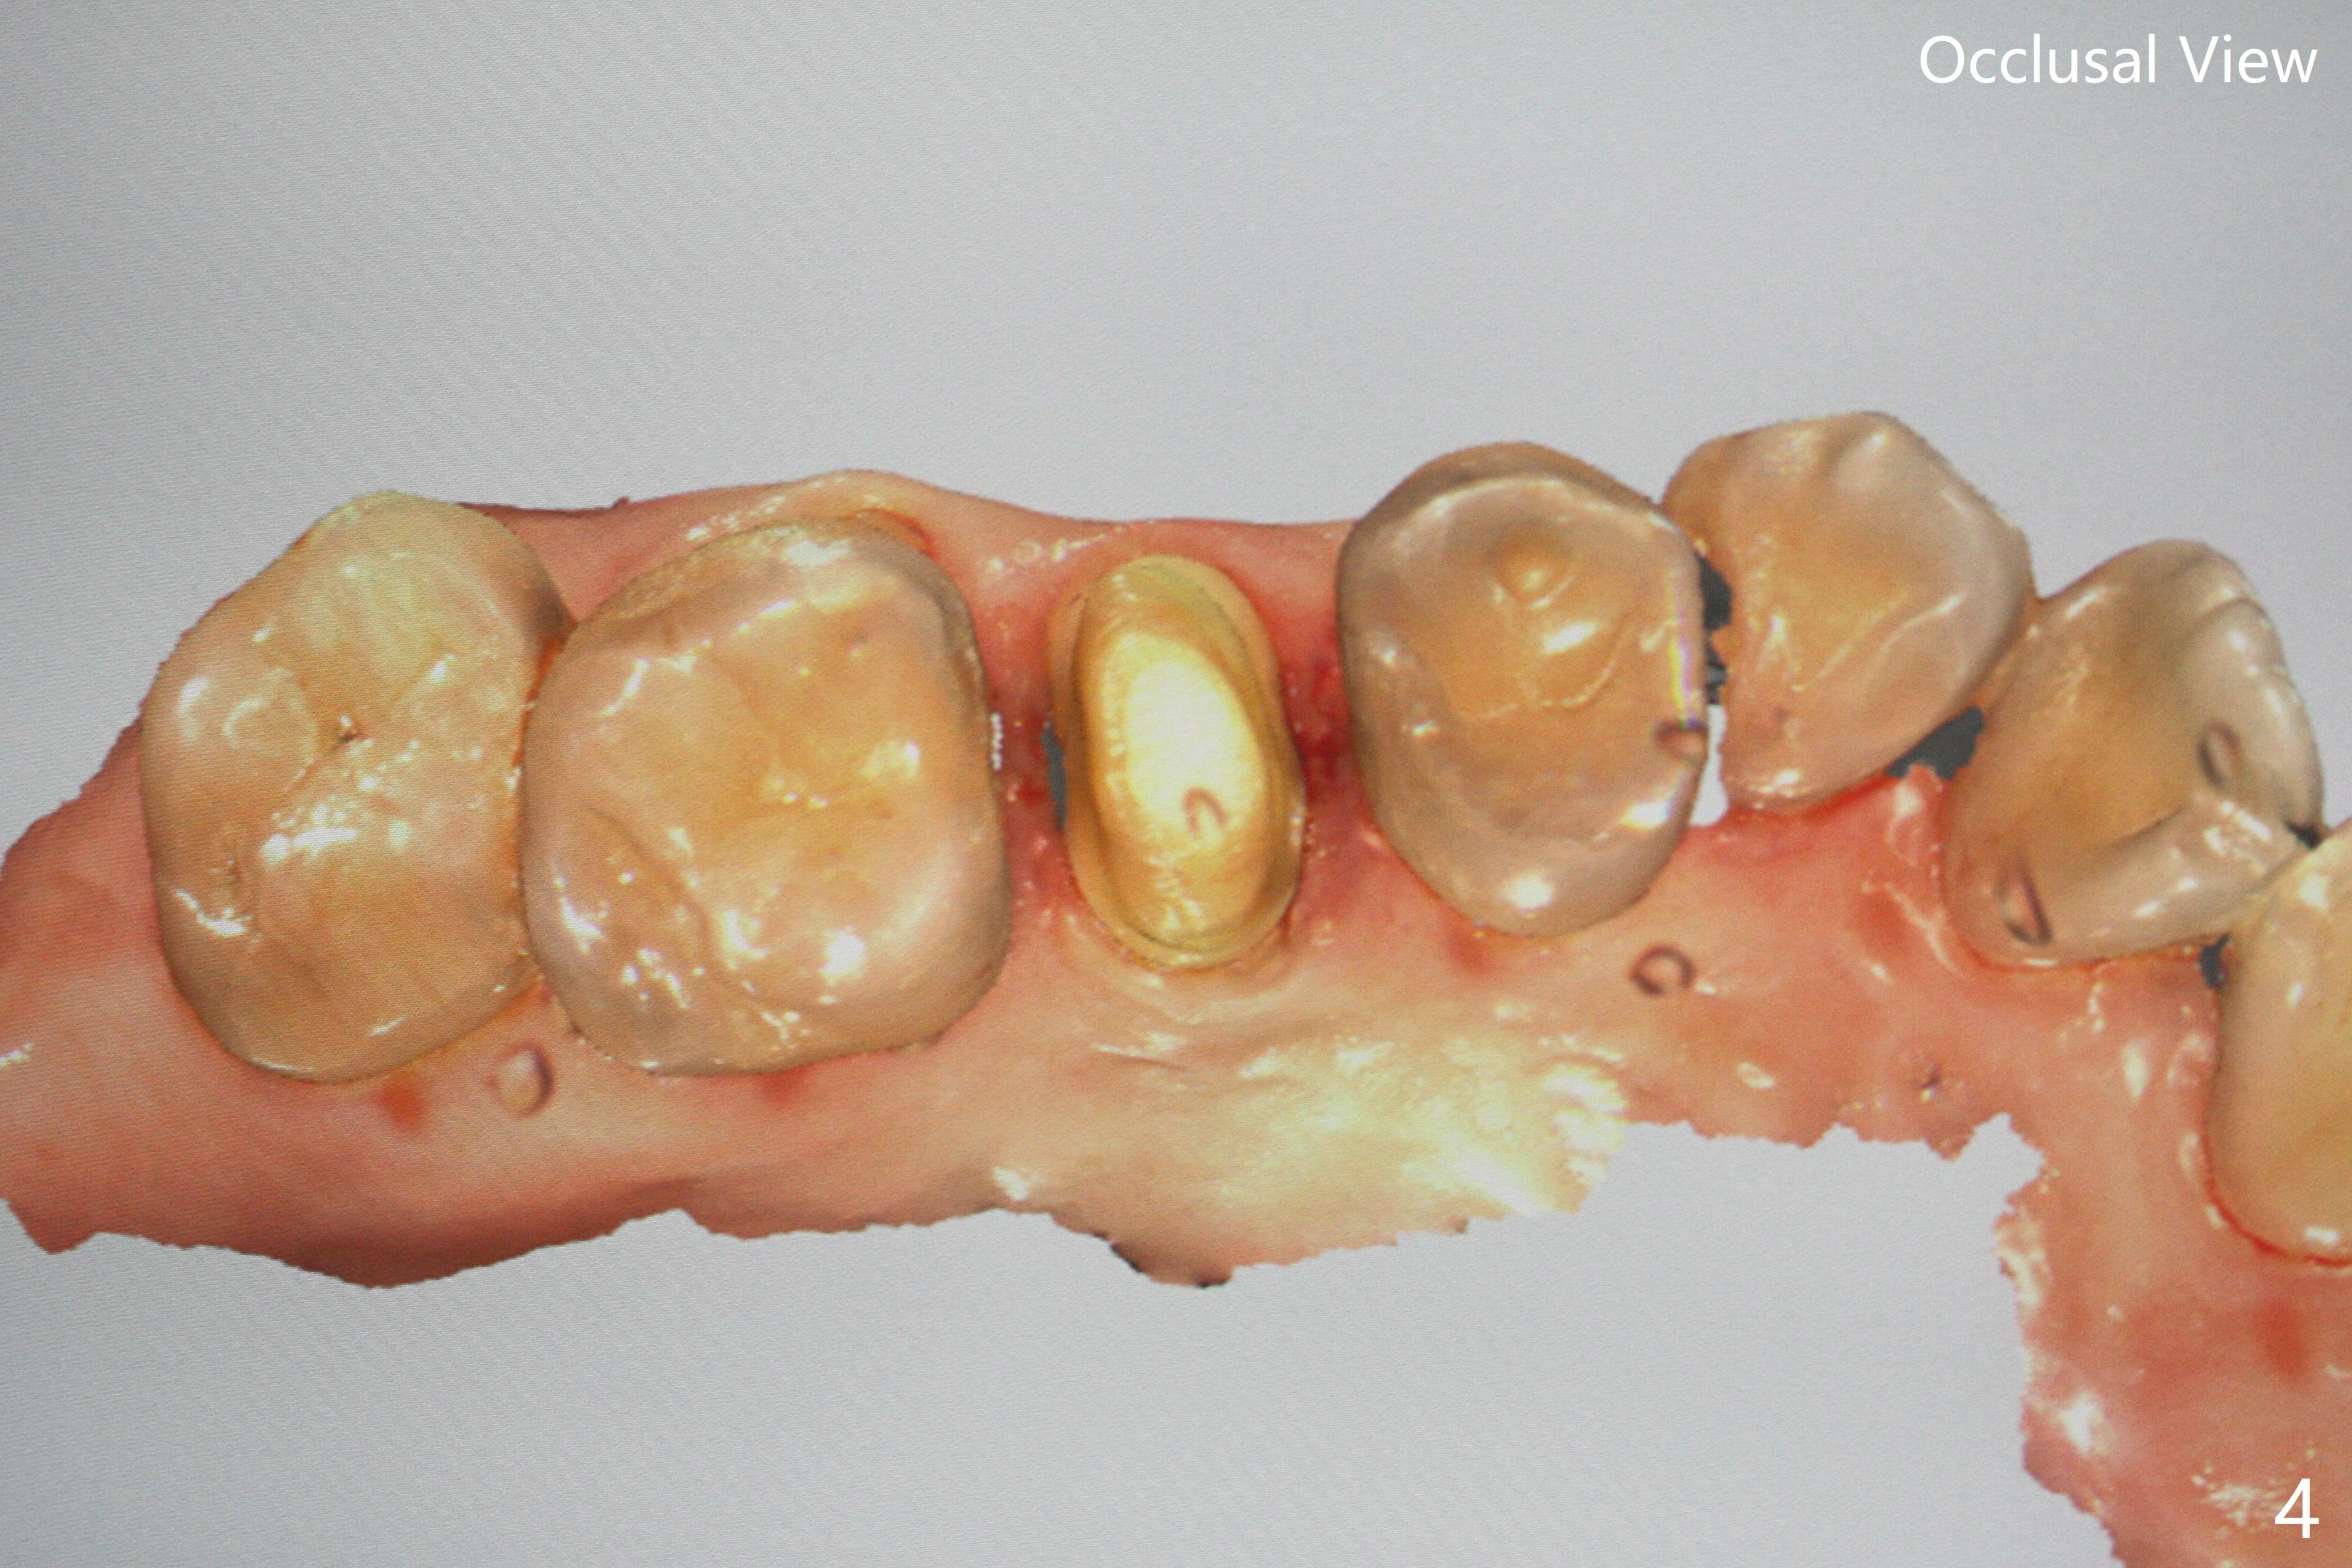

52岁女去年在外州开始4号牙根管治疗(图一),由于新冠病毒和搬家而拖延治疗,现在要求完成根管治疗(图二,三),B: 颊侧(主牙胶尖:20/.04);L: 舌侧(旋转锉:20/.04)。Shining口扫(图四(咬合面观),五(舌侧观),六(颊侧观;对合:局部托牙 (RPD)))。为了保险起见,要求实验室制作两个牙冠:取模,口扫。帮助实验室建立完善数字化系统,从而帮助临床工作。备牙边缘清晰(图八)。牙冠边缘与数字模型(图九)和牙齿吻合,天衣无缝。

Shining Oral Scanner and Crown Prep Margin

Root canal therapy (RCT) was initiated for the tooth #4 of a 52-year-old lady out of state approximately 8 months earlier (Fig.1). The patient requested finishing the treatment and permanent crown fabrication. The buccal (Fig.2 B (master cone 20/.04)) and lingual (L (rotary file 20/.04))) canals fuse near the apex. RCT was done with insertion of 20/.04 and 20/.06 master cones in the buccal and lingual canals, respectively, followed by composite build-up (Fig.3). With basically shoulder margin (not feather margin, chamfer margin ok), it is easy to scan (Fig.4-6 (RPD: removable partial denture)). Return to Oral Scanner Xin Wei, DDS, PhD, MS 1st edition 06/05/2021, last revision 06/25/2021